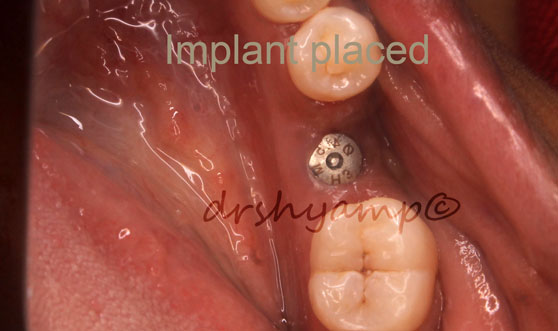

single molar dental implant

single molar dental implant

single molar dental implant

single molar dental implant

single molar dental implant

single molar dental implant

single molar dental implant

single molar dental implant

single molar dental implant

single molar dental implant

single molar dental implant

single molar dental implant

single molar dental implant

single molar dental implant

single molar dental implant